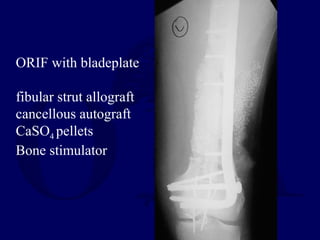

35 yo 

MVC

Open femur with

segmental bone

loss

I&D

ExFix

Beads

ORIF with bladeplate

fibular strut allograft

cancellous autograft

CaSO4 pellets

Bone stimulator

8 months

FWB without pain

return to work